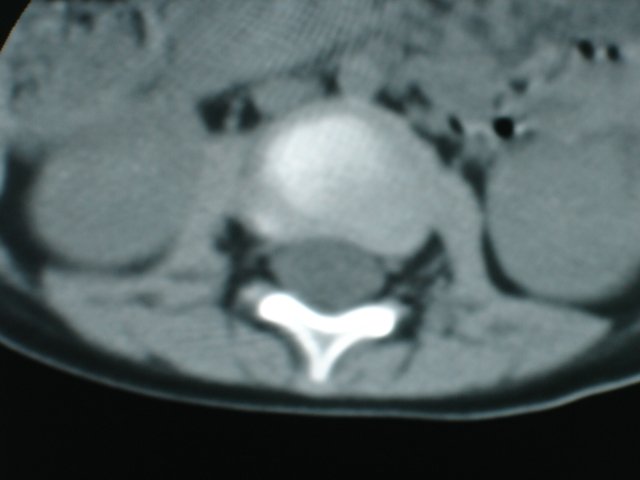

病人男性,一岁半.外伤后腰痛两天.外院x片报腰1压缩性骨折.追问病史,一年前曾有过持续高烧史.血常规及血沉结果未出.

椎体周围见类软组织密度影,椎体见虫蚀样破坏,考虑tb.性。

椎体骨质破坏,椎体周围见软组织密度影.椎体结核

椎体破坏明显,周围软组织肿胀,椎间盘未见明显受累.结核

椎体结核合并冷脓肿形成。

椎体破坏明显,周围软组织肿胀,椎间盘未见明显受累.考虑椎体结核合并冷脓肿形成。

体破坏明显,周围软组织肿胀,椎间盘未见明显受累.考虑椎体结核合并冷脓肿形成.注意排除嗜酸性肉芽肿